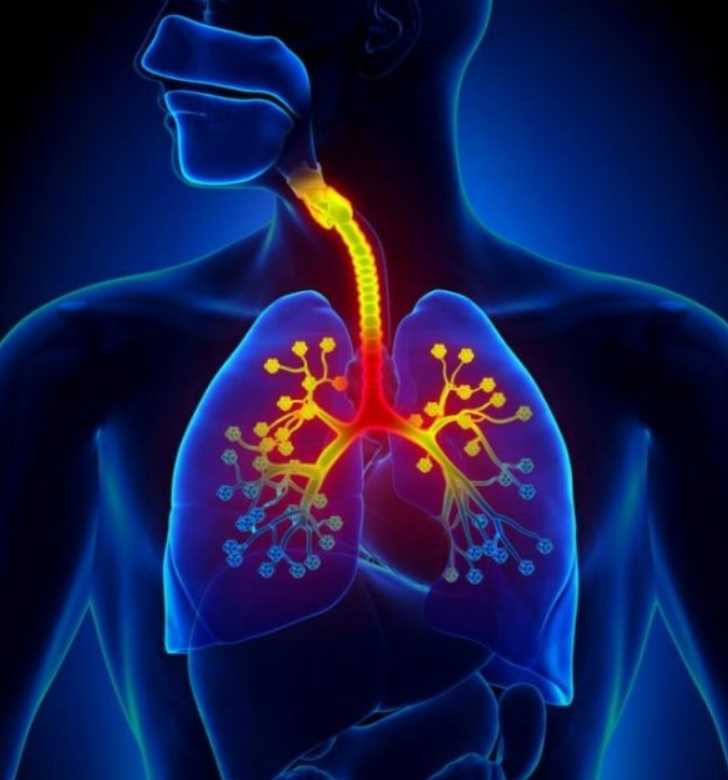

Бронхит – заболевание дыхательной системы, при котором происходят воспалительные процессы в бронхиальном дереве. Одни из основных признаков болезни — значительное повышение температуры тела и кашель. Но иногда бывает и бессимптомное течение бронхита. Как диагностировать его в этом случае и какие методы лечения использовать, узнайте далее.

Бронхи – очень чувствительная к различным воздействиям часть легких. Воспаление их тканей может развиться по разным причинам.